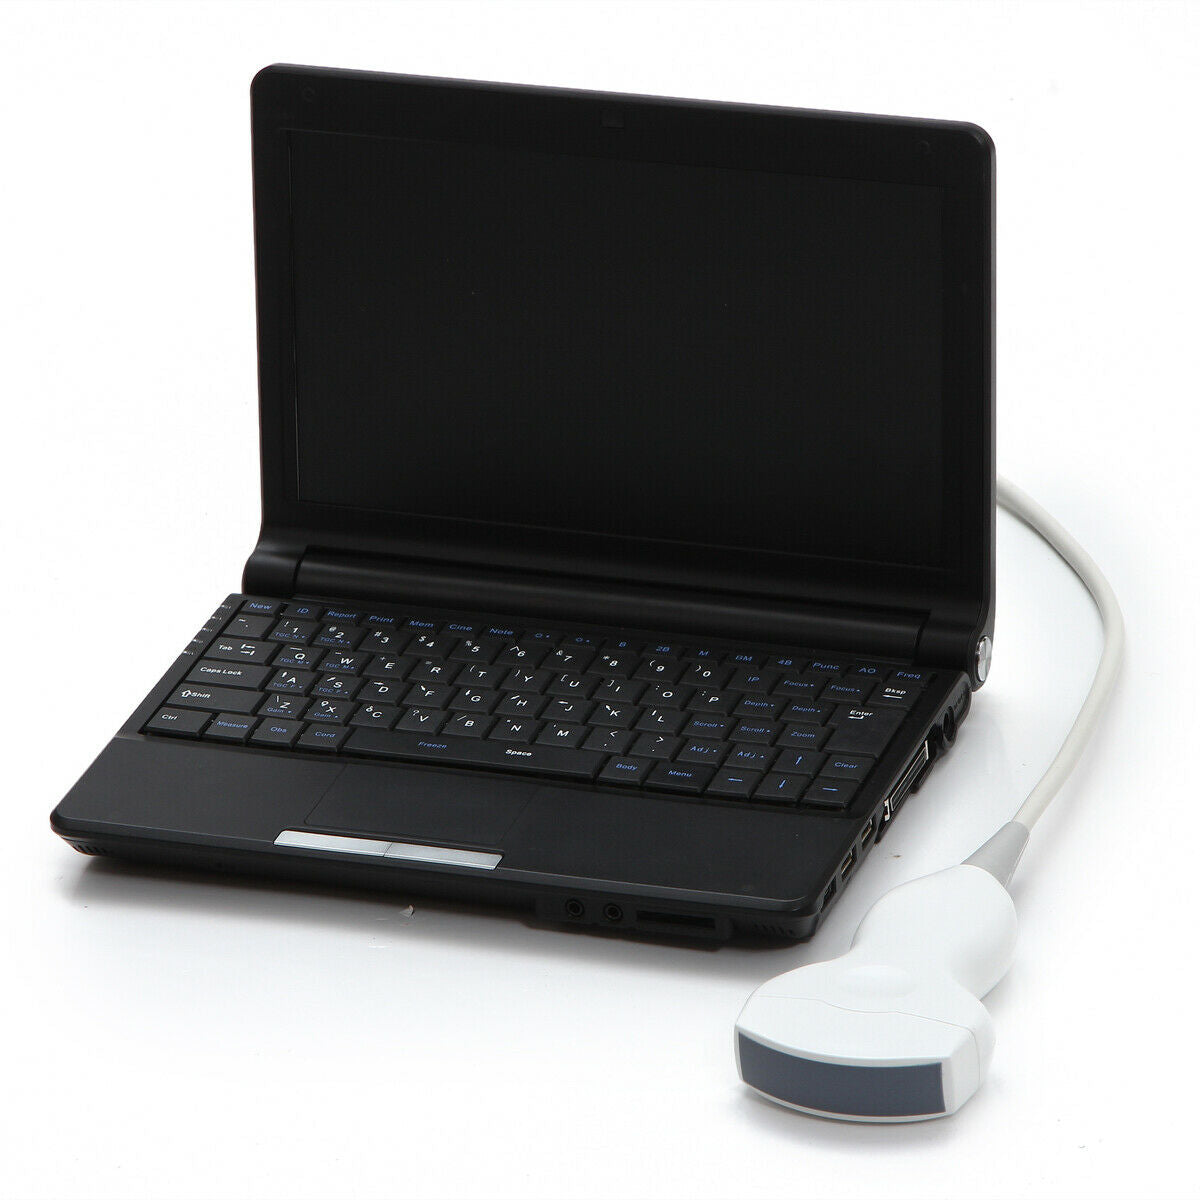

DIAGNOSTIC ULTRASOUND MACHINES FOR SALE

Ultrasound Scanner Laptop Machine Ultrasonic Machine Convex Rectal Transducer

Sale price$ 0.82

Regular price$ 1.00